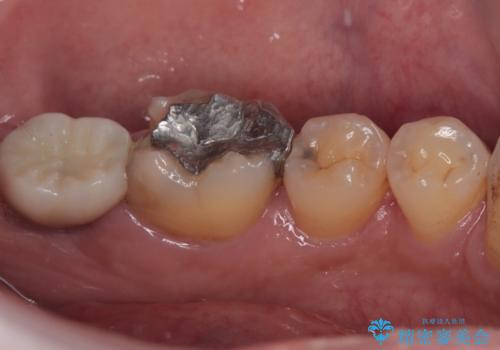

- 左下の歯が欠けてしまったとのことで来院された患者様です。

大きな銀歯が装着されており、その周りからむし歯が広がっている状態でした。

特に症状はなく、神経組織も健全な状態であったため、むし歯を全て取り切った後にフルジルコニアクラウンにて補綴することとしました。